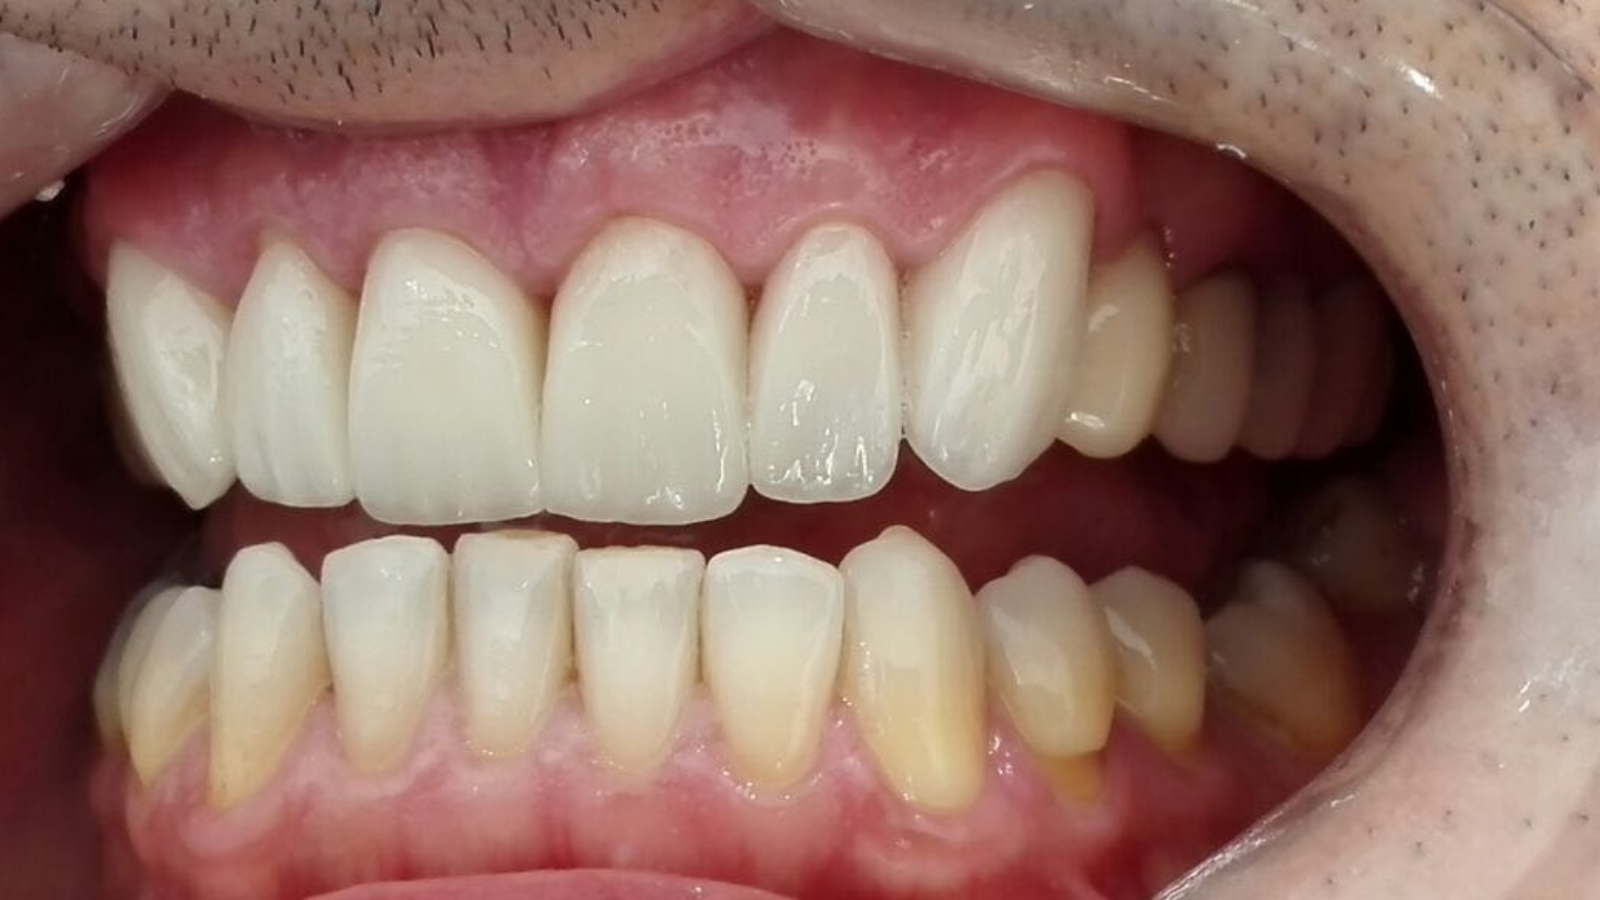

Réhabilitation esthétique après orthodontie : full-zircone & disilicate de lithium

Une jeune patiente arrive en fin de traitement orthodontique pour un déficit esthétique.

La difficulté réside dans la réalisation de prothèses différentes dans le même secteur : jongler avec la full-zircone et le disilicate de lithium.

Ce challenge fut le sujet de mon mémoire du DU d’esthétique de Strasbourg en 2008.

L’expérience et l’investissement dans le digital depuis 2017 rendent le résultat plus prévisible.

Images :